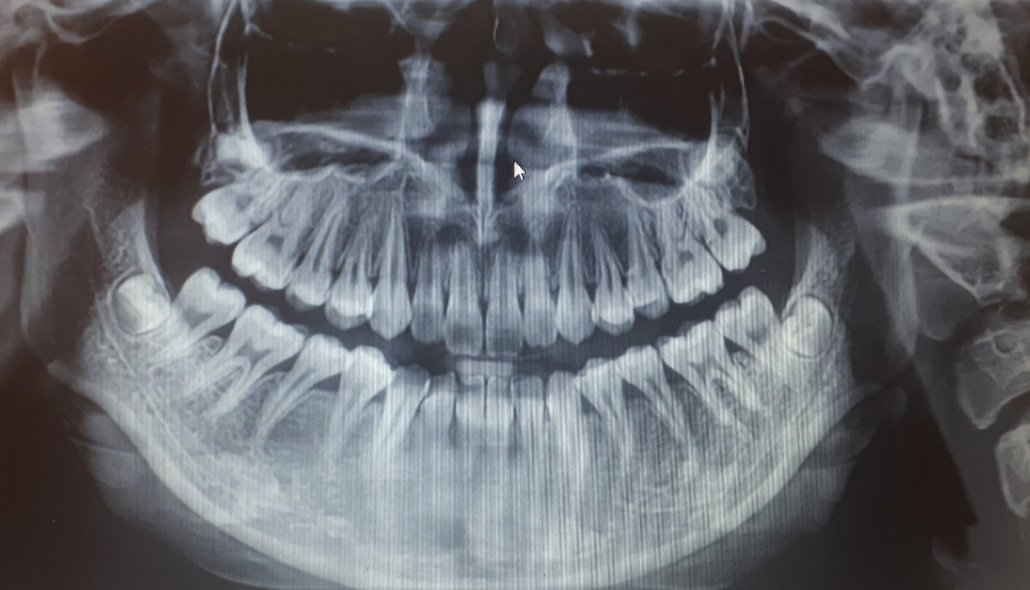

snímka, ktorú ste mi zaslali, sa na stránke Modrého koníka zobrazí len v nízkom rozlíšení, nemôžem si ju nijak zväčšiť ani upravovať. Preto mi nie je umožnené náležite ju zhodnotiť.

Na určenie diagnózy existuje štandardný postup, ktorý zahŕňa samotné vyšetrenie v zubolekárskom kresle, odobranie anamnézy (otázky ohľadom vášho zdravia a prípadných problémov, s ktorými k zubnému lekárovi prichádzate) a pomocné vyšetrenia (jedným z ktorých je práve zhodnotenia röntgenovej snímky).